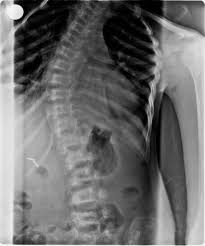

Vertebrae / The Lumbar Vertebrae Radiology Key : In humans, they are a series of 33 bonesthat run from the base of the skull to the coccyx.

In humans, they are a series of 33 bonesthat run from the base of the skull to the coccyx. 493 likes · 12 were here. Anatomy of the vertebral column (spine), including vertebrae structure, joints, ligaments and neurovasculature. Vertebrae overview anatomy for diablo valley college anatomy and physiology. Its appearance is different from the other spinal vertebrae. They each consist of an anterior vertebral body, and the vertebral body forms the anterior part of each vertebrae. Vertebrae are the 33 individual, interlocking bones that form the spinal column. The confusion about these two terms is high among many people because of the close relationship between the two terms. One of the bony segments of the spinal column | meaning, pronunciation, translations and examples. The bones that make up the spinal column. Usually in english, the latin diphthong ae is anglicized as /i/, a long e sound. All vertebrae share a basic common structure. The separation of vertebrae into caudal and precaudal portions appears rather problematic.

The vertebrae in each region have unique features that help them perform their main functions. Anatomy of the vertebral column (spine), including vertebrae structure, joints, ligaments and neurovasculature. Discs between vertebras in lumbar region are the ones with the widest surface of the spine and the task of these discs are to carry the load and to protect the spine. This vertebra supports the skull. Plural of vertebra specialized 2.